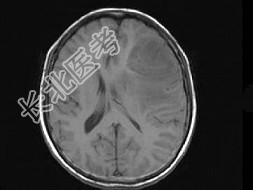

- 单项选择题女,52岁, 头痛伴呕吐2周,根据所提供图像, 最可能的诊断是 ( )

A、转移瘤

B、星形细胞瘤Ⅱ级

C、星形细胞瘤Ⅰ级

D、少枝胶质细胞瘤

E、脑脓肿